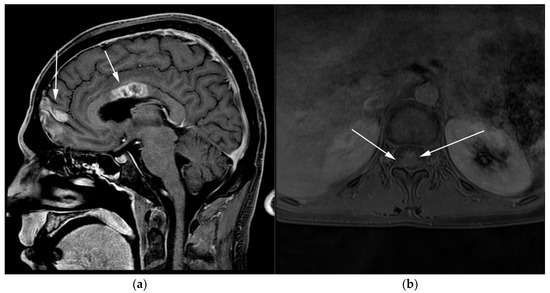

Figure 10.

Imaging in the same patient 1 year later—patient developed new brain and spine lesions. (a) Sagittal T1 post-contrast MRI images show heterogenous mass within the body of the corpus callosum (posterior arrows) as well as within the frontal cortex (anterior arrows). (b) Axial T1 post-contrast MRI of the spine shows ill-defined enhancement within the spinal cord (arrows), consistent with leptomeningeal disease.

WM patients can also present with splenomegaly with or without focal lesions and lymphadenopathy typically within the axillary, retroperitoneal, and/or inguinal nodal stations (Figure 12). Cranial nerve deficits can be a manifestation of Bing–Neel syndrome, a rare CNS manifestation seen in WM disease [45,48,52,54]. In Bing–Neel syndrome, neurological symptoms can be directly related to infiltration by lymphoplasmacytic cells or indirectly result from the deposition of circulating IgM immunoglobulin on the brain parenchyma, spinal cord, or cranial or peripheral nerves (Figure 13). Additionally, 18F-FDG PET/CT plays an important role in monitoring therapeutic response after treatment initiation, especially with rituximab. WM patients tend to show elevated IgM levels, known as an IgM flare, which may mimic progressive disease. Imaging plays a pivotal role to differentiate between an IgM flare and true progression, thus obviating the need for repeated marrow biopsy [52]. Imaging may also help in excluding the development of myelodysplastic syndromes, acute leukemia, or DLBCL transformation [52].

Figure 13.

Patient with known diagnosis of lymphoplasmacytic lymphoma (LPL). (a) Coronal T1 post-contrast of the brain image shows diffuse leptomeningeal enhancement (black arrows). (b) Axial MRI T1 post-contrast image of the lumbosarcal spine in the same patient shows diffuse epidural soft tissue thickening and enhancement of the cauda equina nerve roots (white arrows). (c) Microscopic examination of the lymph node shows effaced architecture by infiltrative diffuse sheets of atypical lymphoid cells with plasmacytoid morphology. Tumor cells are positive for CD20 and are monotypic, expressing kappa or lambda light chains. (Original magnification 400×, H&E stain). CNS involvement in is an extremely rare variant known as Bing–Neel syndrome (BNS).